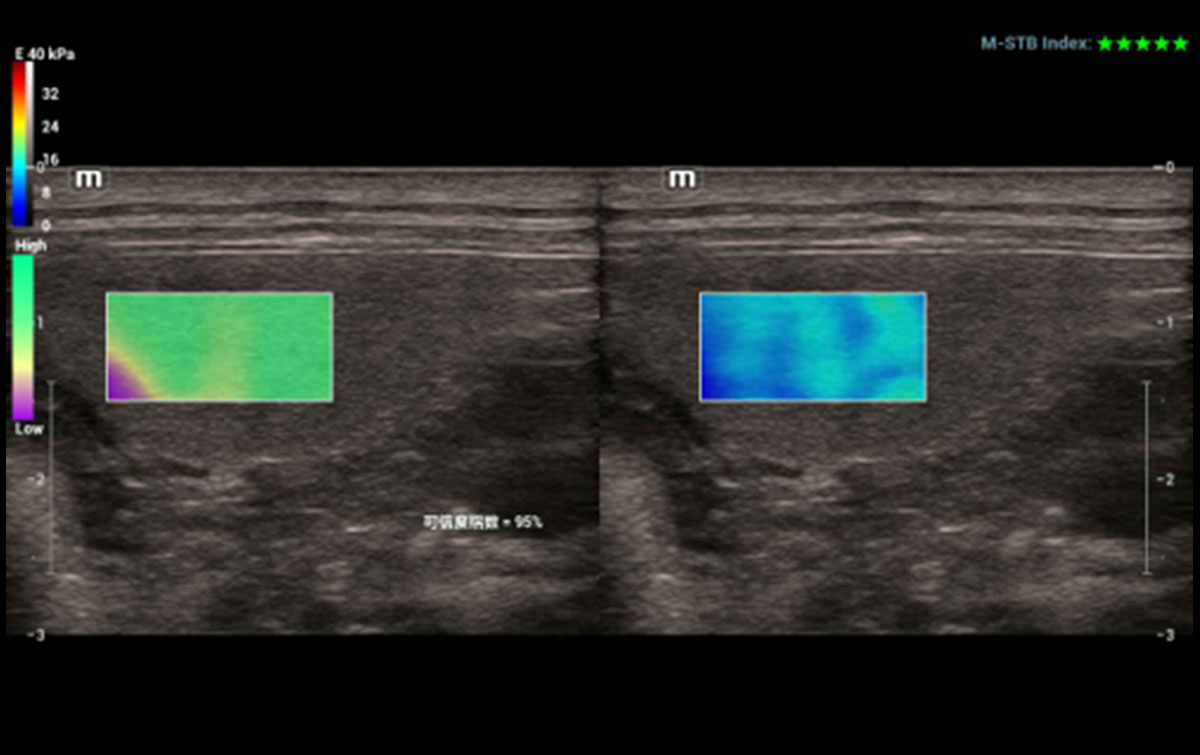

Evaluación de rigidez innovadora – STE

Sound Touch Elastography (STE) ofrece imágenes de elastografía de ondas de corte 2D en tiempo real. Proporciona un análisis cuantitativo basado en la evaluación de la rigidez del tejido.